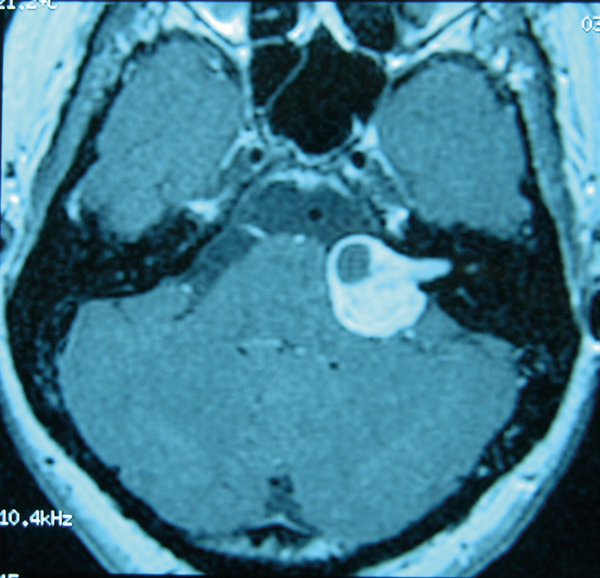

Figure 1: Glomus tympanicum in right middle ear seen with otoendoscopy.

- Primary or secondary. Primary tinnitus is idiopathic and may or may not be associated with sensorineural hearing loss (SNHL). Secondary tinnitus is associated with a specific underlying cause other than SNHL e.g. acoustic neuroma, glomus tumour (Figure 1) or vascular anomaly, otosclerosis, chronic otitis media.

For secondary tinnitus, treatment depends on the causal condition, e.g. surgical removal for a glomus tympanicum.